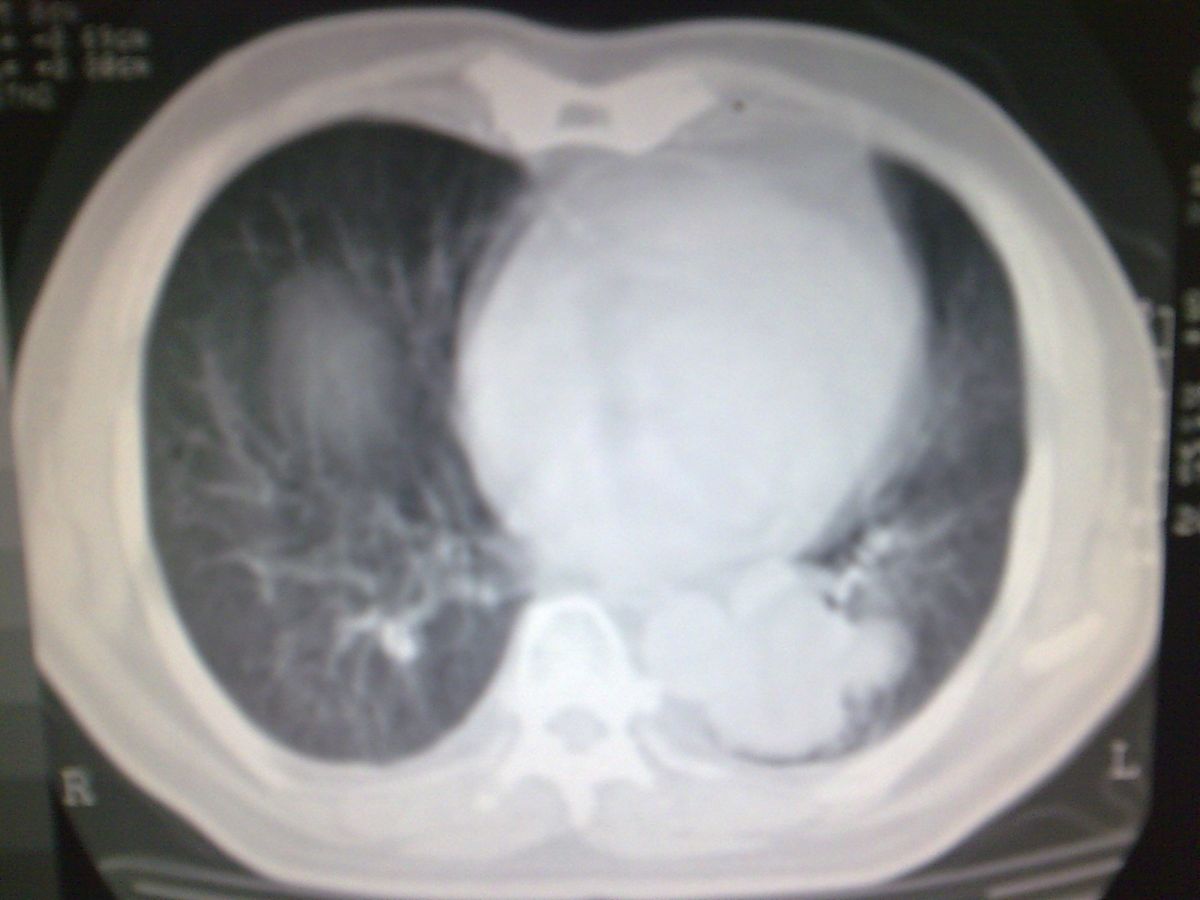

标题: CT19282:男性,70岁,咳血, [打印本页]

标题: CT19282:男性,70岁,咳血,

图片少了些,考虑周围性肺癌

考虑周围性肺癌

周围型肺癌。

考虑左下肺周围性肺癌。

考虑左下周围型肺癌可能性大。

考虑左肺下叶周围型肺癌可能。